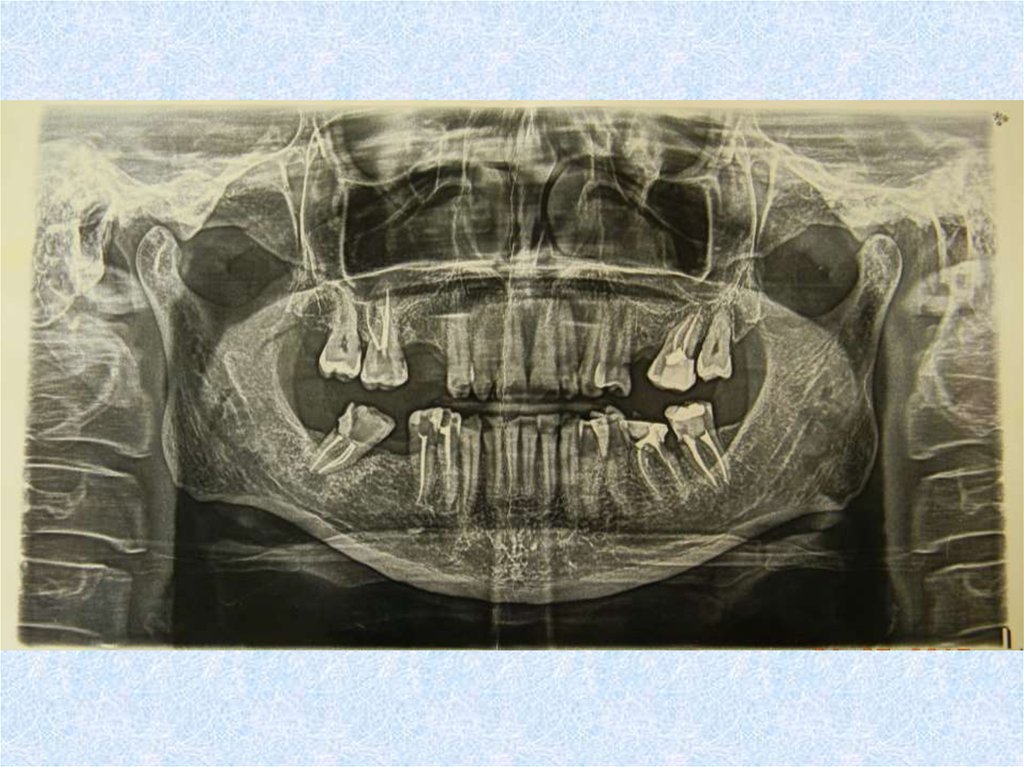

Клинический случай №1

Невправляемый вывих диска обоих ВНЧС

• Открывание рта 20 мм

• Щелчки возникли месяц назад впервые

• Через три недели возникло ограничение открывания

рта

• Не было никаких стоматологических вмешательств

• Скачок роста этим летом

Модели загипсованы в привычной окклюзии при

двустороннем вывихе диска